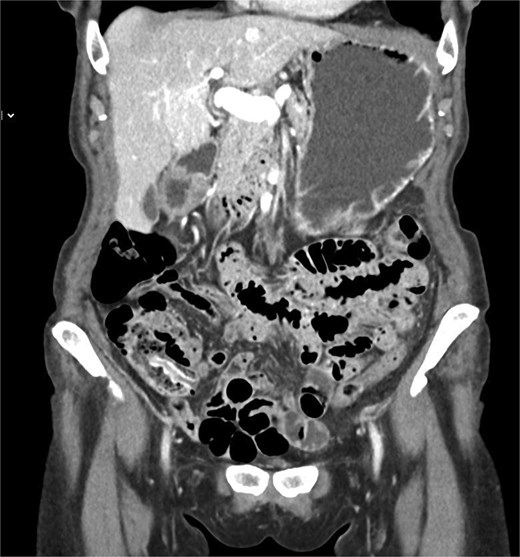

The outpatient abdominal CT images were reviewed, and the diagnosis of an inverted appendix was confirmed (Fig. 2).

Coronal contrast-enhanced CT scan demonstrating an elongated structure projecting into the cecal lumen from the appendiceal orifice, consistent with an inverted appendix.

Radiologic imaging plays a central role in confirming the diagnosis and excluding malignancy. CT typically demonstrates a tubular structure invaginating into the cecum, which correlates with the endoscopic impression of a polypoid lesion at the appendiceal orifice [5, 9]. Cross-sectional imaging is particularly useful in distinguishing benign inversion from neoplastic causes, as appendiceal carcinoid tumors may appear as mural thickening with or without enhancement [5]. Positron emission tomography or magnetic resonance imaging may also be used to further characterize lesions when suspicion for malignancy is high [5]. Recognition of these radiologic patterns helps avoid unnecessary intervention while ensuring that pathologic conditions are not overlooked.